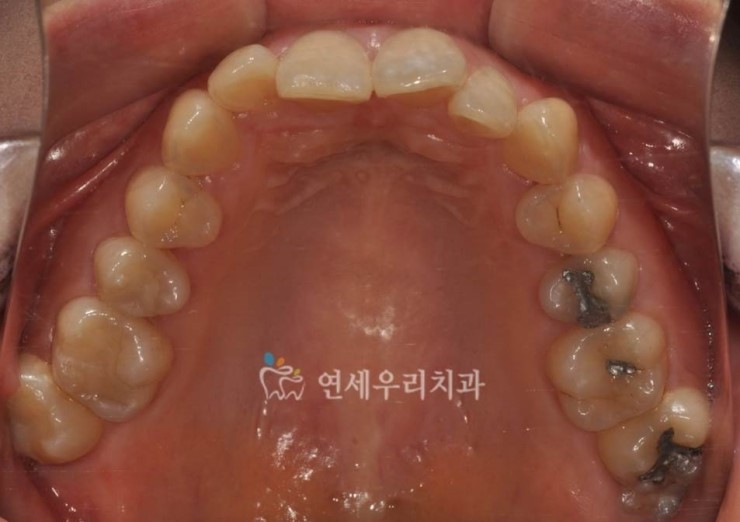

을 주소로 내원하신 20대 여성분인데 환자분의 오른쪽 어금니 교합은 아래 송곳니가 살짝 튀어나온 부분을 제외하면 어느 정도 괜찮을 것 같습니다.그런데 반대쪽 어금니를 보면 윗니에 가려져 아랫니가 거의 보이지 않는 상태에서 아랫니 어금니가 혀 쪽으로 넘어지면서 윗니 아랫니가 전혀 맞물리지 않는 상태입니다.가위교합(scissors bite)이라고 하는데 윗니는 뺨 쪽으로, 아랫니는 혀 쪽으로 완전히 엇갈린 교합의 양상이며, 이 교합은 시간이 지남에 따라 점점 심각해집니다.따라서 오랜 시간이 지나면 상하 어금니 치주(치경)가 나빠지고 어금니 전체를 발치하는 경우도 흔합니다.또한 정면 사진에서 위쪽 화살표를 보면 좋지 않은 교합 때문에 잇몸 마모증(Cervical abfraction)도 있습니다.

윗니 어금니가 뺨 쪽으로 많이 어긋난 상태입니다.치아가 조금씩 구부러져 있는 부분은 가위의 교합 교정을 하는 과정에서 자연스럽게 정돈된다고 생각됩니다.(교정치료를 치아를 다듬는 것으로만 생각할 수 있지만, 삐끗한 부분이 정돈되는 과정이 가장 쉽고 빠르게 중요한 것은 상하교합을 기능적으로 정상화하는 것입니다.)) 직업상의 이유로 장치를 부착할 수 없어 제거해야 하는 기간이 일시적으로 있었음에도 약 1년 정도의 기간으로 가짜 교합을 정상 교합에 맞추면서 치료를 종결하였습니다.